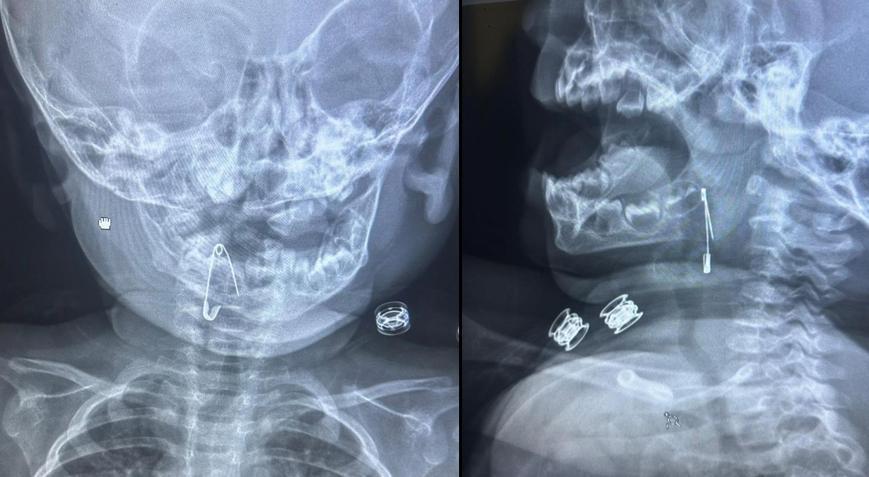

Güroymak ilçesinde 8 aylık bebek, evde bulunan çengelli iğneyle oynarken onu yuttu. Öksürmeye başlayan minik çocuğun, hastanede çekilen röntgen sonucu çengelli iğneyi yuttuğu fark edildi.

Güroymak Devlet Hastanesi’nden Tatvan Devlet Hastanesi’ne ambulansla sevki gerçekleşen minik çocuk, Kulak Burun Boğaz Hastalıkları Uzmanı Operatör Dr. Hakan Tuhan tarafından yapılan başarılı operasyonla sağlığına kavuştu. Çengelli iğnenin saplı olduğu soluk borusundan çıkarılan bebek, 2 saatlik gözlemin ardından taburcu edildi.

Konuyla ilgili açıklamada bulunan Kulak Burun Boğaz Hastalıkları Uzmanı Operatör Dr. Hakan Tuhan, “8 aylık bir bebek, Bitlis’in Güroymak ilçesinden tarafımıza danışıldı. Güroymak ilçesinde çekilen röntgen sonucunda çengelli iğnenin soluk borusunun girişinde olduğunu teyit ettik. Yapılan müdahaleler sonucunda çengelli iğneyi çıkardık. Çıkardıktan sonra iki saat kadar gözlem altında tuttuk hastamızı. Daha sonrasında herhangi bir komplikasyonla karşılaşmadık ve sorunsuz bir şekilde taburcu ettik” dedi.